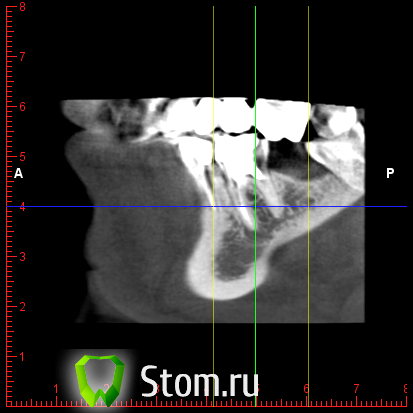

y2006 Опубликовано 3 мая, 2012 Автор Поделиться Опубликовано 3 мая, 2012 (изменено) прошу проконсультировать по поводу зуба 46. вопрос стоит в лечении и протезировании коронкой или удалении и заменой имплантом, правда ли что есть показания к удалению - перфорация корня? файлы для Romexis_Viewer по ссылке: (чуть позже)к сожалению не знаю как по другому выложить Изменено 3 мая, 2012 пользователем y2006 Ссылка на комментарий

y2006 Опубликовано 3 мая, 2012 Автор Поделиться Опубликовано 3 мая, 2012 снимок Ссылка на комментарий

y2006 Опубликовано 3 мая, 2012 Автор Поделиться Опубликовано 3 мая, 2012 (изменено) какие есть методы лечения? или есть необходимость в дополнительных проекциях? Изменено 3 мая, 2012 пользователем y2006 Ссылка на комментарий

y2006 Опубликовано 5 мая, 2012 Автор Поделиться Опубликовано 5 мая, 2012 (изменено) КТ IMAGES.rar46 зуб Изменено 5 мая, 2012 пользователем y2006 Ссылка на комментарий